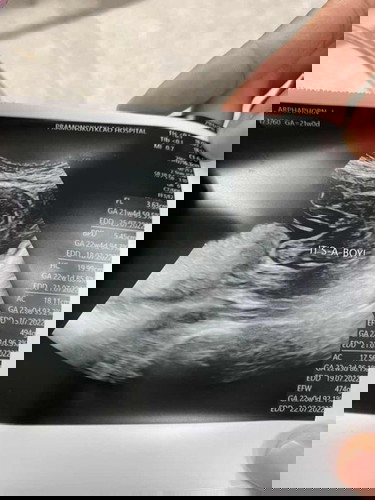

หมอบอกคุนแม่ได้ลูกชายแบบนี้ผุ้ชาย100%ไหมค่ะ

น่าจะ100% แล้วละค่ะ

ผู้ชายค่ะ